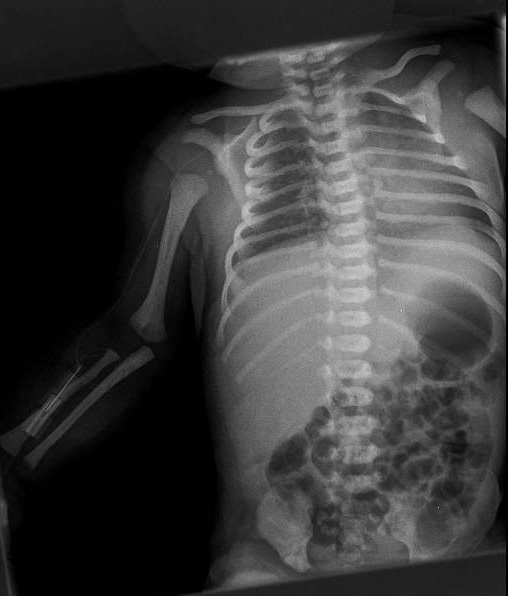

Se le realizaron radiografía de tórax, ecografía abdominal y cerebral sin hallazgos patológicos además de ecocardiografía sin cardiopatía estructural demostrable y analítica con valores dentro de la normalidad.